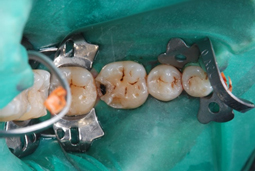

十分な機械的強度を有しているため、これまではペーストタイプを使っていた臼歯部咬合面のCR修復でも問題なく使えます(図2参照)。

図2 左下第一大臼歯の頬面の破折と遠心隣接面の象牙質う蝕をフロアブルレジンで修復。